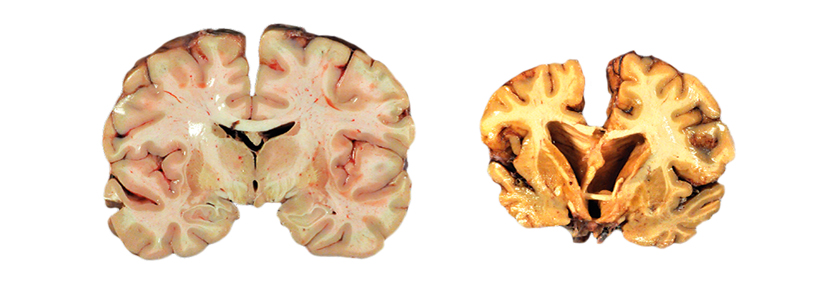

Das Parkinson-Syndrom ist eine chronische neurologische Erkrankung, die durch degenerative Veränderungen im extrapyramidal-motorischen System (EPMS) ausgelöst wird. Insbesondere in der Substantia nigra im Bereich der Basalganglien kommt es zu einem fortschreitenden Untergang von melaninhaltigen Neuronen. Folgen sind eine verminderte Synthese von Dopamin mit relativen Acetylcholinüberschuss. Auch andere Neurotransmitter wie Serotonin und Noradrenalin können aus dem Gleichgewicht geraten, was zu vielseitigen neurologischen Störungen führen kann. In der Regel schreitet die Erkrankung progredient voran und zeigt einen typischen stadienhaften Verlauf.